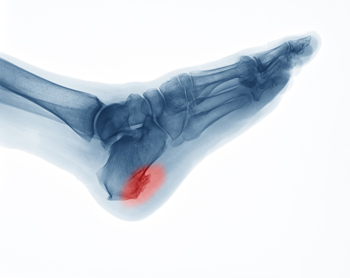

How Heel Pain Can Develop

Many people across the globe suffer from heel pain. It can occur from a variety of foot conditions, including plantar fasciitis, arthritis, or possibly from an Achilles tendon injury. There are patients who develop heel spurs, and the symptoms are often similar to those of plantar fasciitis, which can consist of heel pain in the morning after arising. If an injury has occurred, it may also result in a heel fracture. Common symptoms of this type of heel condition can include swelling, excessive pain, difficulty walking. There are many methods of treating heel pain, and it is strongly suggested that you consult with a podiatrist who can determine what the best healing technique is for you.

Causes of Heel Pain

Heel pain is often associated with plantar fasciitis. The plantar fascia is a band of tissues that extends along the bottom of the foot. A rip or tear in this ligament can cause inflammation of the tissue.

Achilles tendonitis is another cause of heel pain. Inflammation of the Achilles tendon will cause pain from fractures and muscle tearing. Lack of flexibility is also another symptom.

Heel spurs are another cause of pain. When the tissues of the plantar fascia undergo a great deal of stress, it can lead to ligament separation from the heel bone, causing heel spurs.